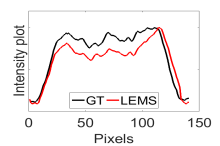

The calculated correlation coefficient (), SNR, as well as CNR values for all tested methods in the synthetic phantom experiment are shown in Table II. As seen in Table II, the proposed NCBC method achieved the highest , CNR as well as SNR values when compared to that of other tested methods. Visual results from the bias-corrected DW-MR synthetic phantom data produced using different tested methods is shown in Fig. 2(c-i). It can be observed that the MCBC, LEMS, and proposed NCBC method were able to achieve the best level of bias correction when compared to the other tested methods. This is particularly apparent in the peripheral zone (PZ) of the prostate gland as highlighted using red ROIs in Fig. 2(a-i), where intensity inhomogeneities are still present to a significant degree in the bias-corrected phantom data produced using the LS, SCIC, SGD and BCFCM methods, while strong inhomogeneity correction performance is achieved using MCBC, LEMS, and the proposed NCBC method. Furthermore, it can be observed that NCBC exhibited minimal intensity inhomogeneities when compared with MCBC and LEMS, particularly in the area that is highlighted using Red ROIs. To better represent the outperforming of proposed NCBC method in terms of bias correction using synthetic phantom, the data intensity profiles corresponding to the drawn blue line in Fig. 3(a) are shown in Fig. 3(b) for uncorrected data (red color plot) versus ground truth data (black color plot) and in Fig. 3(c-i) for corrected data using different tested methods (red color plots) versus ground truth data (black color plots). As the intensity profiles of Fig. 3(b-i) show, NCBC method was resulted in an intensity profile with the most flatness and less amount of variation compared to the intensity profiles of uncorrected image as well as reconstructed images using other tested methods as such confirms the better performance of proposed NCBC method in terms of bias field correction.